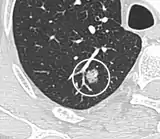

A "notch sign".[9]

- Margin morphology: a spiculated margin is a risk factor for cancer.[8] Benign causes tend to have a well defined border, whereas lobulated lesions or those with an irregular margin extending into the neighbouring tissue tend to be malignant.[10] In particular, spiculations are highly predictive of malignancy with a positive predictive value up to 90%.[9] Also, a "notch sign", which is an abrupt indentation of the nodule, increases the risk of cancer, but may also be found in granulomatous diseases.[9]